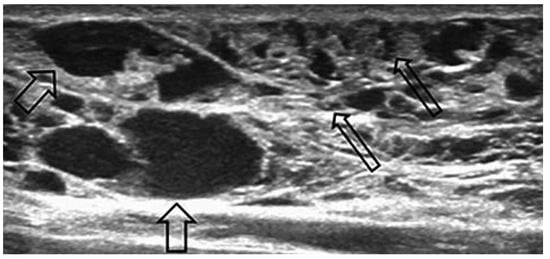

Case report A 22-year-old male experienced a presyncopal spell while studying for a university examination [...]